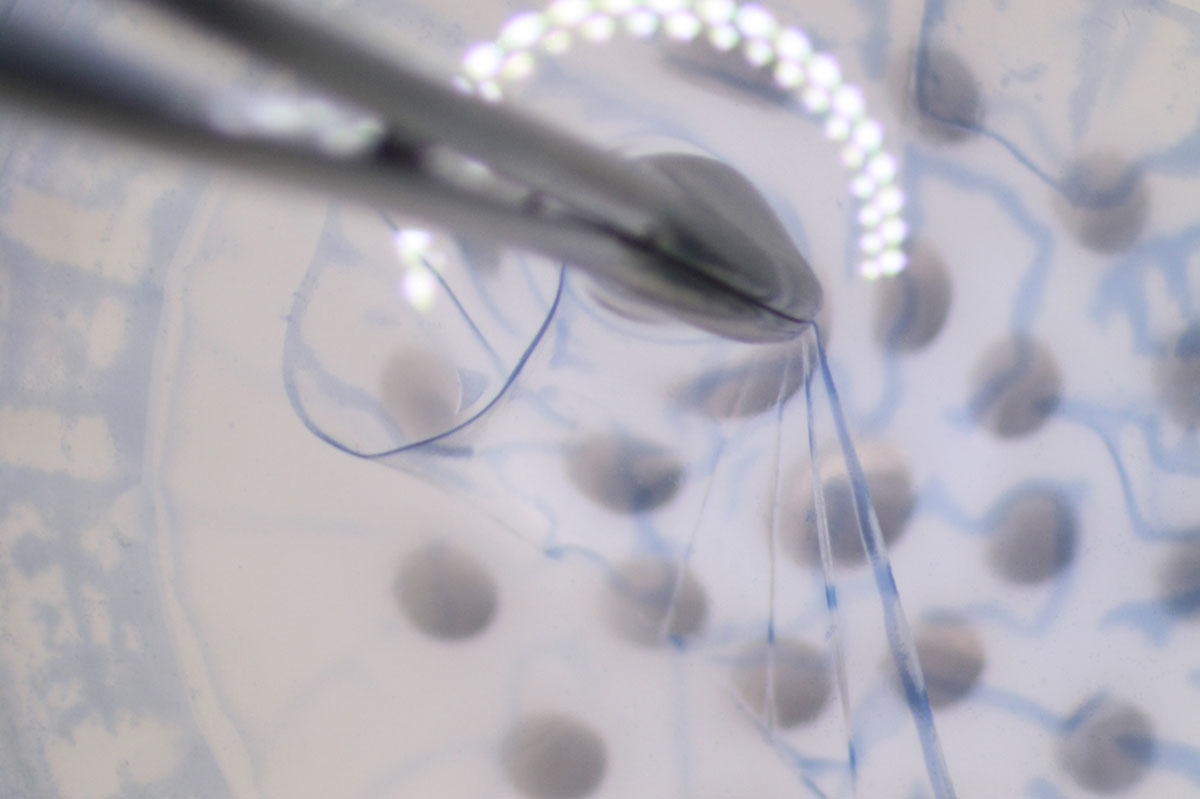

Doch bei welchen Erkrankungen kann eine Transplantation zur letzten Therapiemöglichkeit werden? Welche Vorteile hat ein Teiltransplantat für Patienten? Wie lange müssen Betroffene auf ein Transplantat warten? Diese und weitere Fragen rund um die Augenhornhauttransplantation beantwortet Dr. Thomas Kern, Spezialist für Augenhornhauttransplantationen sowie Linsen- und Netzhautchirurgie, im Interview.

Patienten sehen insbesondere morgens unscharf. Ein erhöhtes Blendungsempfinden schränkt wiederum das Autofahren bei Dämmerung und Nacht ein. Das Lesen fällt Patienten zunehmend schwerer. Müssen Betroffene ihre berufliche Tätigkeit einstellen und sind in ihrem Lebensalltag stark eingeschränkt, ist die Transplantation einer Spenderhornhaut notwendig.